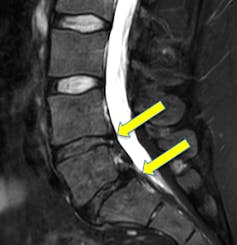

Or une hernie discale cause surtout des symptômes lorsqu’elle comprime un nerf responsable des sensations dans les jambes. Donc en l’absence de douleur dans une jambe selon un trajet bien précis, il est fort probable qu’une hernie vue en imagerie ne soit pas la source du problème.

Vous saisissez donc toute la problématique autour de cet examen : pour savoir si une hernie ou un pincement discal est bien la source d’un problème constaté, il faut prendre en compte tous les éléments cliniques (histoire de la douleur, manifestations, données de l’examen…). Car, comme on l’a pointé, il est impossible en voyant une image seule de savoir si l’anomalie qui apparaît engendre des douleurs ou non.